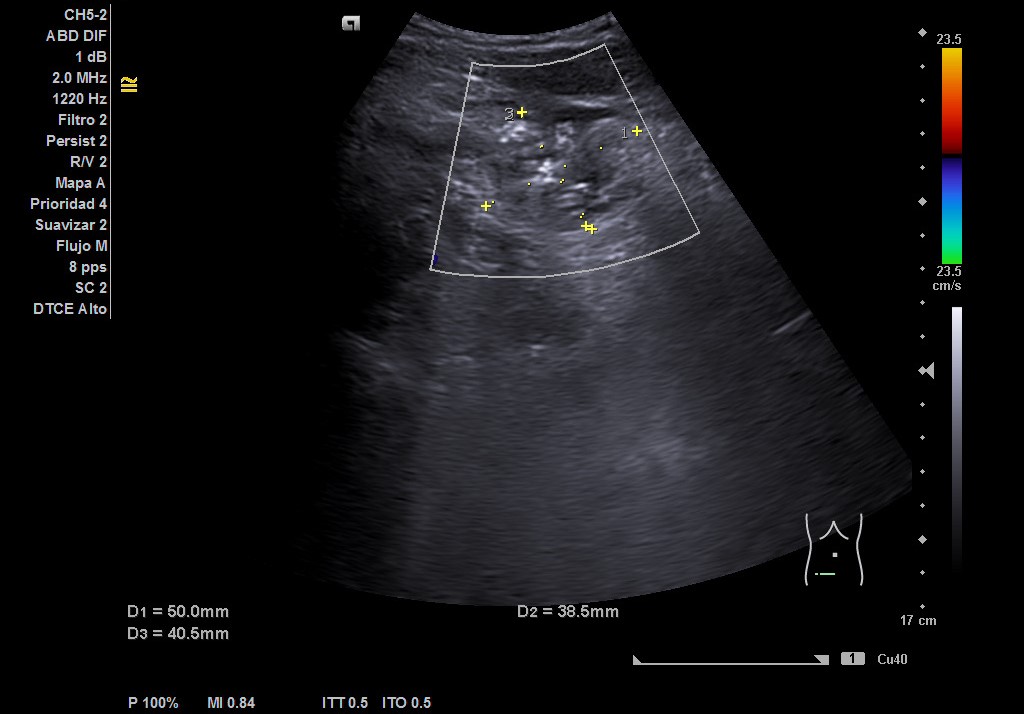

Hallazgos ecográficos

Hígado de tamaño, forma y ecoestructura conservadas, con parénquima homogéneo. Vena porta de calibre conservado.  Ausencia de signos de dilatación de la vía intra o extrahepática. Vesícula biliar de paredes finas, sin contenido ecogénico en su interior. Páncreas de características normales. Riñones de tamaño y localización conservada, sin hidronefrosis. En FID imagen heterogénea delimitada, de 50x30 mm, con posible edema de pared y focos ecogénicos en su interior.